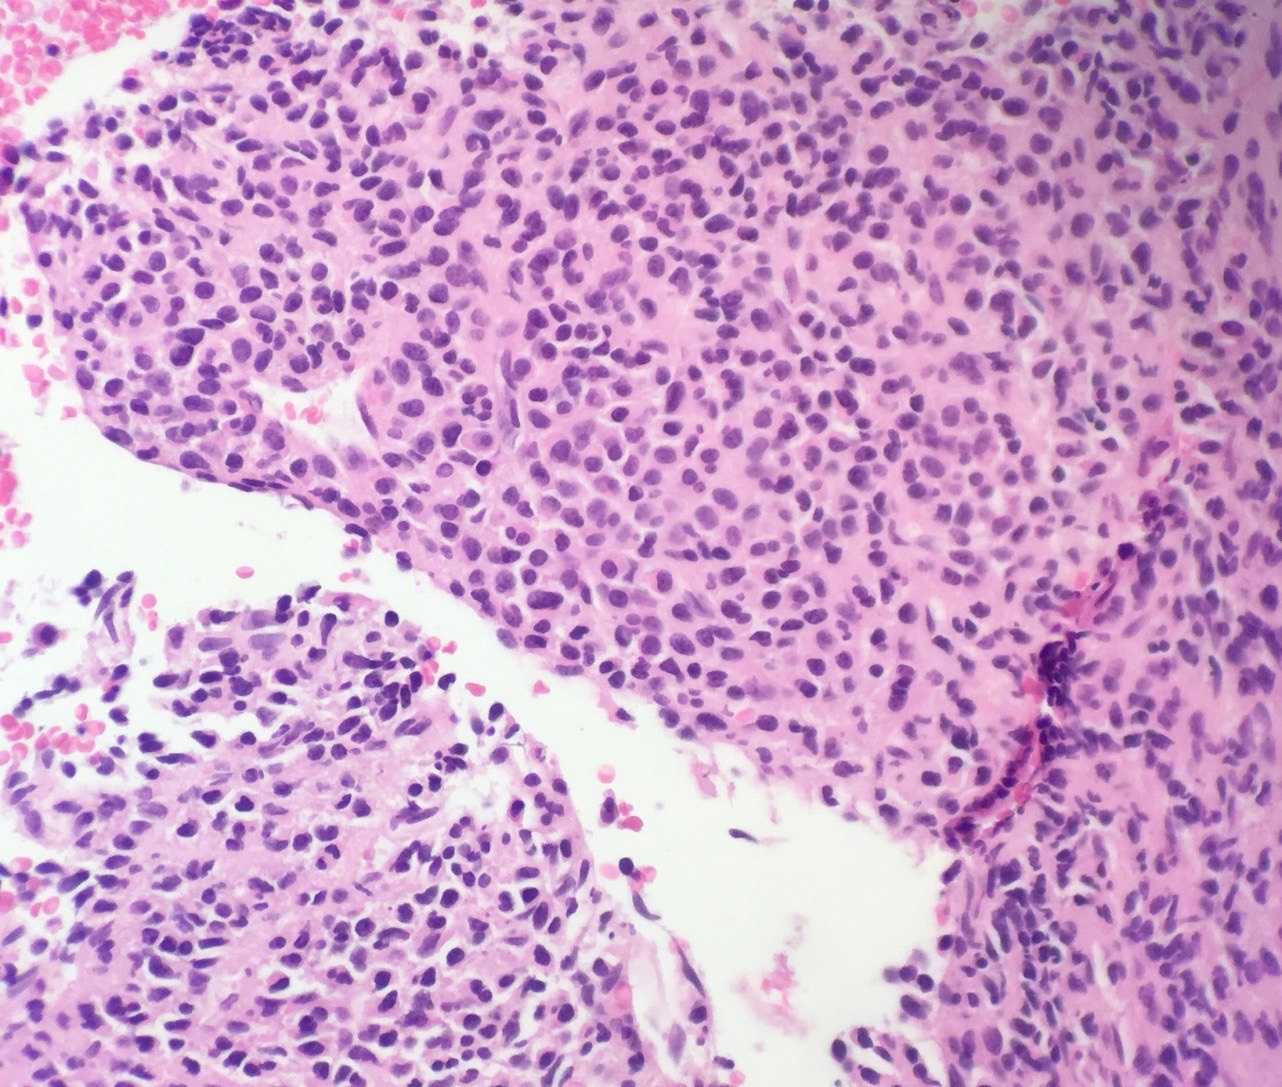

Microscopic (histologic) description

- Core biopsy (Am J Clin Path 1987;87:342):

- Interstitial clusters, nodules or sheets of plasma cells

- Areas of bone marrow may be spared with preserved hematopoiesis, other cases may have diffuse involvement and markedly suppressed hematopoiesis

- Prominent osteoclastic activity may be seen

- IHC to quantify plasma cells (CD138), stains for Ig kappa and lambda to establish clonality

Microscopic (histologic) images

Contributed by Genevieve M. Crane, M.D., Ph.D. and Tapan Bhavsar, M.D., Ph.D.

Cytology description

- Cytology can assess plasma cell morphology (e.g., mature, immature, plasmablastic) but number of plasma cells present may vary substantially from the core biopsy

- Mature plasma cells: oval with abundant basophilic cytoplasm, perinuclear hof, round eccentric nuclei, clock face chromatin and indiscernible nucleoli

- Immature plasma cells: higher nuclear to cytoplasmic ratio, more abundant cytoplasm and hof region compared to plasmablastic, more dispersed chromatin, often prominent nucleoli

- Plasmablastic: less abundant cytoplasm with little or no hof region, fine reticular chromatin, large nucleus (> 10 microns) or large nucleolus (> 2 microns) (Blood 1998;91:2501)

- Pleomorphic: multinucleated, polylobated